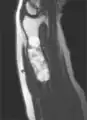

X-ray showing enchondromas localized in the humerus of a 37-year-old patient affected with Ollier disease

Enchondromas localized in the upper part of the humerus of the same patient